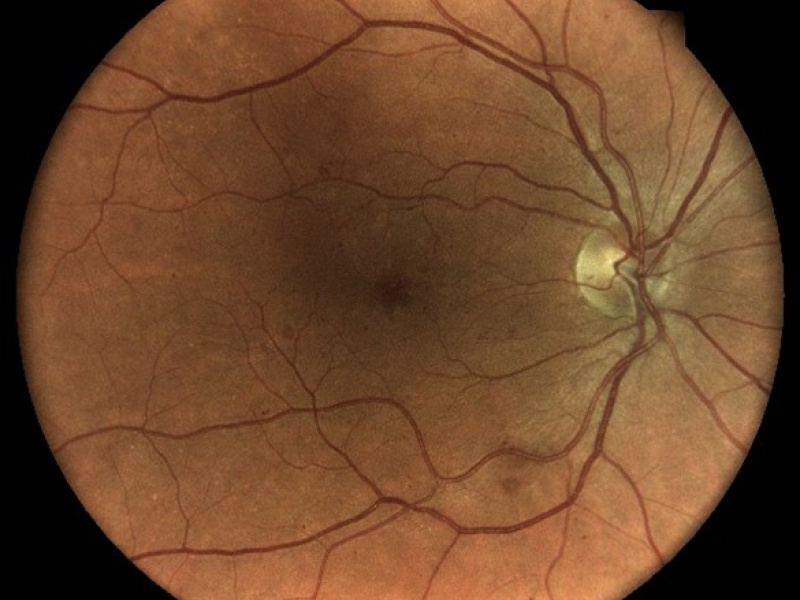

Technológia TrueColor Confocal od iCare prekračuje limity konvenčných zariadení na zobrazovanie fundusu a SLO tým, že kombinuje tie najlepšie výhody z oboch. Jednoducho povedané, fundus fotoaparáty poskytujú vysokú vernosť farieb a systémy SLO produkujú vysokú ostrosť, čistotu, celkovú presnosť a detaily v obrazoch. Keď sa tieto funkcie skombinujú, vytvárajú obraz krajiny sietnice špičkovej kvality vo verných farbách.

Aby bolo možné diagnostikovať a sledovať bežné patológie, ako je diabetická retinopatia, zariadenia na zobrazenie očného pozadia musia byť schopné kombinovať veľké rozlíšenie, vysoký kontrast a vysokú vernosť farieb. To umožňuje zachytiť malé znaky a detaily a rozlišovať medzi jednotlivými zmenami, ktoré by ste mohli inak ľahko prehliadnuť. Zatiaľ čo štandardné systémy SLO majú vysokú jasnosť, ostrosť a kontrast, tradičné fundus kamery ponúkajú vysokú vernosť farieb, konvenčné zobrazovacie riešenia tieto dve veci nekombinujú!

Zobrazovacie systémy fundus generujú obrazy s prirodzenými farbami iba vtedy, ak využívajú biele svetlo: to znamená, že všetky vlnové dĺžky viditeľného spektra sú prítomné v osvetľovacom lúči použitom na získanie obrazu sietnice. Na získanom zábere je možné rozlíšiť rôzne farebné detaily.

iCare sa vyznačuje používaním bieleho svetla LED v kombinácii s konfokálnou optikou, ktorá pomáha získavať vysokokvalitné snímky sietnice so zvýšenou vernosťou farieb.